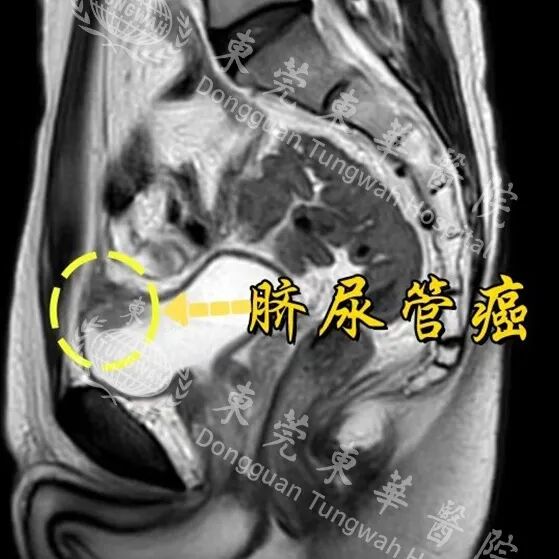

反复血尿2个月,49岁男子查出"百万分之一"罕见癌!

49岁的王先生(化名)从未想过,自己反复出现的无痛性血尿,会牵出一个“隐匿杀手”,并最终指向一个连泌尿外科医生都极少遇见的恶性肿瘤——脐尿管癌。